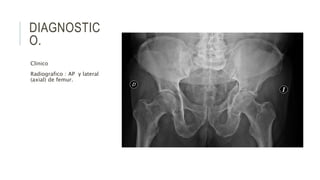

DIAGNOSTIC

O.

Clinico

Radiografico : AP y lateral

(axial) de femur.